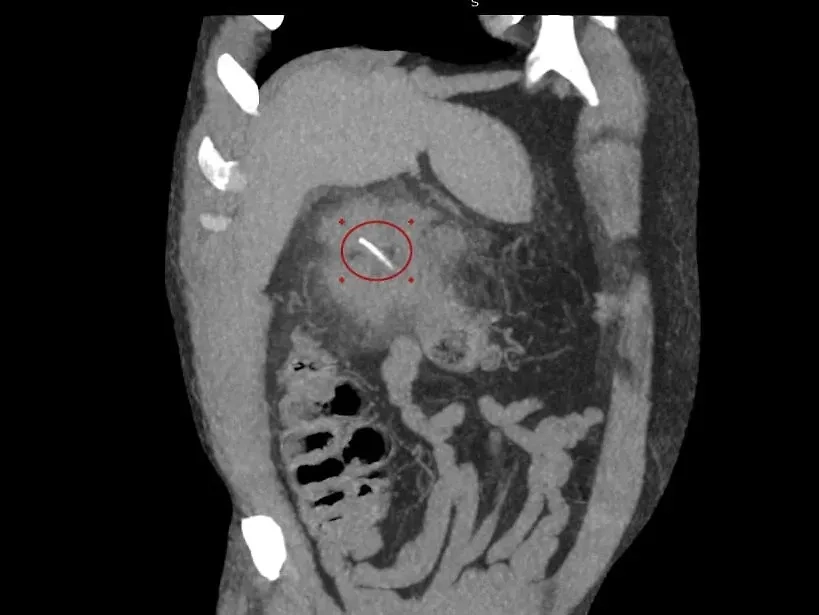

Врачи Луховицкой больницы спасли рыбака, которому рыбья кость проткнула кишечник. В медицинское учреждение обратился 64-летний мужчина с жалобами на периодические боли в правом подреберье. Проведённая диагностика выявила инородное тело костной плотности в проекции правого фланга толстой кишки.

«Пациент нуждался в экстренном хирургическом вмешательстве. Мы провели КТ-диагностику, после чего вскрыли абсцесс под спинальной анестезией и удалили гной. Операция прошла успешно», — поделился заведующий хирургическим отделением больницы Илья Луньков.

Рыбья кость около трёх сантиметров длиной проделала отверстие в стенке толстой кишки мужчины в области печени. Рыбу пациент ел почти месяц назад, проглотив и кость. Сначала он не почувствовал никакого дискомфорта, но спустя некоторое время появились периодические боли в подреберье. В больнице провели операцию, сейчас мужчина чувствует себя хорошо и готовится к выписке.